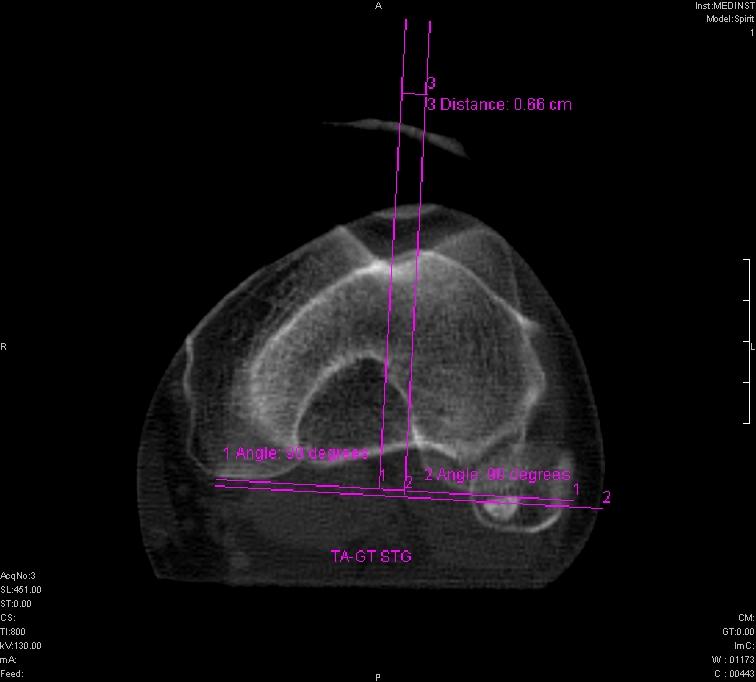

- măsuratori de stabilitate rotuliană;